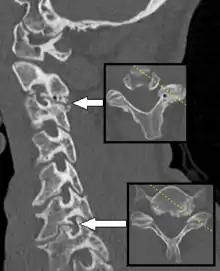

Спондильоз (spondylosis; грец. «spondylos»- хребець; син. деформуючий спондильоз) — інволюційний процес поступового зношування і старіння анатомічних структур хребта, що супроводжується дистрофією зовнішніх волокон передніх або бокових відділів фіброзного кільця, випинанням його під тиском м'якотного ядра, що зберегло свій тургор, відкладенням і осифікацією передньої поздовжньої зв'язки і утворенням крайових кісткових розростань (остеофітів) уздовж осі хребта тільки по колу передніх і бічних відділів.

Спондильоз являє собою особливу патологію, при якій кісткова тканина суглобів розростається, при чому утворюються так звані остеофіти, тобто, небажані утворення кісткової тканини (по мірі наростання кістковий виріст поширюється до сусіднього хребця, тоді як від сусіднього хребця утворюється такий же виріст, в деяких випадках окостеніння починається на рівні міжхребцевого диска). В особливо важких випадках настає зрощення хребців, від чого страждають судини, нерви і м'язова тканина, а також прилеглі органи.